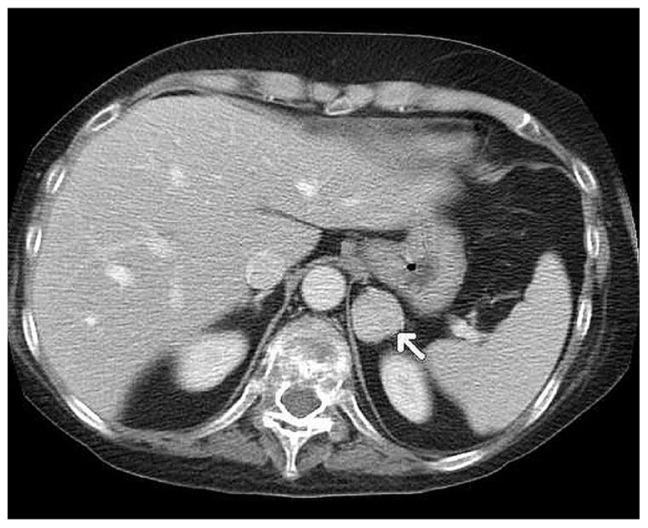

Hypothalamic-pituitary-adrenal axis impairment in anorexia nervosa is marked by hypercortisolemia, and psychiatric disorders occur in the majority of patients with Cushing's syndrome. Here we report a patient diagnosed with anorexia nervosa who also developed Cushing's syndrome. A 26-year-old female had been treated for anorexia nervosa since she was 17 years old, and also developed depression and paranoid schizophrenia. She was admitted to the Department of Endocrinology, Metabolism, and Internal Medicine with a preliminary diagnosis of Cushing's syndrome. Computed tomography revealed a 27 mm left adrenal tumor, and she underwent laparoscopic adrenalectomy. She was admitted to hospital 6 months after this procedure, at which time she did not report any eating or mood disorder. This is a rare case report of a patient with anorexia nervosa in whom Cushing's syndrome was subsequently diagnosed. Diagnostic difficulties were caused by the signs and symptoms presenting in the course of both disorders, ie, hypercortisolemia, osteoporosis, secondary amenorrhea, striae, hypokalemia, muscle weakness, and depression.

神经性厌食症的下丘脑-垂体-肾上腺轴功能损害表现为皮质醇增多症,大多数库欣综合征患者都存在精神障碍。在这里,我们报告了一例神经性厌食症患者,其也发展为库欣综合征。一名 26 岁女性从 17 岁开始接受神经性厌食症治疗,还患有抑郁症和偏执型精神分裂症。她因初步诊断为库欣综合征而被收入内分泌、代谢和内科。计算机断层扫描显示左侧肾上腺有一个 27 毫米的肿瘤,她接受了腹腔镜肾上腺切除术。术后 6 个月,她再次入院,此时她没有报告任何饮食或情绪障碍。这是一例罕见的神经性厌食症患者病例报告,该患者随后被诊断为库欣综合征。由于两种疾病的体征和症状出现,诊断存在困难,即皮质醇增多症、骨质疏松症、继发性闭经、条纹、低钾血症、肌肉无力和抑郁。